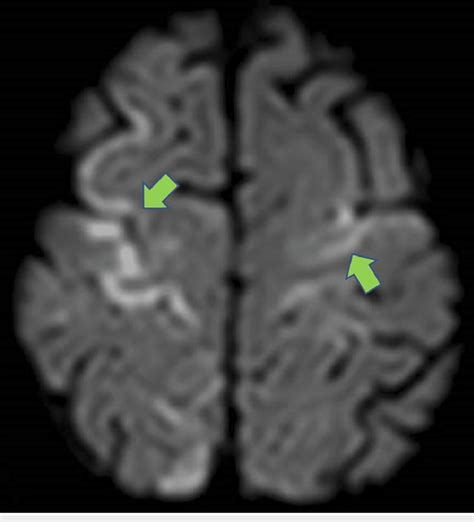

Now, let’s talk about where the rubber meets the road – the clinical applications of Diffusion-Weighted Imaging (DWI) . This technique has revolutionized how we diagnose and manage a variety of medical conditions, particularly neurological ones. The undisputed champion application for DWI is the early detection of acute ischemic stroke . When blood flow to the brain is cut off, brain cells begin to die within minutes. This cell death causes a rapid influx of water into the cells, leading to cytotoxic edema and restricted diffusion. DWI is incredibly sensitive to this restriction, allowing clinicians to identify a stroke within minutes of symptom onset , often long before it’s visible on conventional MRI sequences like T1 or T2. This early detection is absolutely critical because it allows for timely administration of clot-busting medications (thrombolytics) or other interventions, which can significantly improve patient outcomes and reduce long-term disability. It’s like catching a fire when it’s just a spark instead of a raging inferno! But DWI’s utility doesn’t stop at stroke. It’s also invaluable in diagnosing and characterizing brain tumors . DWI can help differentiate between different types of tumors, assess tumor aggressiveness, and monitor response to treatment. For example, some aggressive tumors have areas of restricted diffusion due to high cellularity. Furthermore, DWI plays a key role in evaluating traumatic brain injury (TBI) . It can detect subtle areas of injury, such as diffuse axonal injury (DAI), which might be missed on standard imaging. It helps in understanding the extent of damage and guiding management strategies. Beyond the brain, DWI is also finding increasing applications in imaging other parts of the body. In liver imaging , it can help detect and characterize liver lesions, assess liver fibrosis, and monitor treatment response in conditions like hepatocellular carcinoma. In prostate imaging , DWI is crucial for detecting and localizing prostate cancer, improving the accuracy of biopsies and treatment planning. Even in cardiac imaging , DWI is being used to assess myocardial infarction (heart attack) and monitor heart tissue viability. The versatility of DWI is truly remarkable, offering diagnostic power across a wide spectrum of clinical scenarios. It’s a testament to how understanding the fundamental movement of water can lead to profound clinical insights.

Interpreting Diffusion-Weighted Imaging (DWI) scans can seem a bit daunting at first, but once you understand the basic principles, it becomes much clearer. The most critical thing to remember is that restricted diffusion appears bright on DWI images . Why bright? Because the sequence is designed to attenuate the signal when water diffuses freely, and preserve the signal when diffusion is restricted. So, areas where water molecules can’t move easily – due to swollen cells, tightly packed structures, or other microstructural changes – will stand out as hyperintense, or bright, spots. The most classic example is an acute ischemic stroke . In the early minutes to hours after a stroke, brain cells become damaged, their cell membranes lose integrity, and water rushes in, causing them to swell. This swelling severely restricts the movement of water molecules. Consequently, the affected area lights up brightly on the DWI scan. This is often the very first sign of a stroke visible on MRI. However, it’s crucial to distinguish true restricted diffusion from other phenomena that can also cause bright signals. One important consideration is T2 shine-through . Some tissues naturally have a long T2 relaxation time, meaning they appear bright on conventional T2-weighted images. If these tissues also have some degree of diffusion, their signal might still appear bright on DWI, even if diffusion isn’t truly restricted. This is where the ADC map comes in as your best friend. Remember, the ADC quantifies the actual rate of water diffusion, independent of T2 effects. In areas of true restricted diffusion (like a stroke), the ADC values will be low . In contrast, areas that are bright on DWI due to T2 shine-through will have normal or even high ADC values. So, the combination of a bright DWI signal and a corresponding low ADC value is the hallmark of restricted diffusion and strongly suggests a pathological process like stroke or cytotoxic edema. Another important interpretation point is anisotropy . In tissues like the white matter of the brain, water diffusion isn’t the same in all directions. It tends to follow the direction of the nerve fibers. Multi-directional DWI and ADC tensor imaging can reveal these directional differences, which are crucial for understanding the integrity of white matter tracts. For instance, conditions that damage these tracts, like multiple sclerosis or TBI, can alter the pattern of diffusion. In tumors, DWI can help assess cellularity. Highly cellular tumors often exhibit restricted diffusion (bright on DWI, low ADC), which can help differentiate them from less cellular tumors or other lesions. So, when you’re looking at a DWI scan, always look at the DWI image and the ADC map together. The DWI highlights potential areas of concern, and the ADC map helps confirm whether the signal change is due to true diffusion restriction or something else. It’s this combined interpretation that makes DWI such a powerful diagnostic tool.